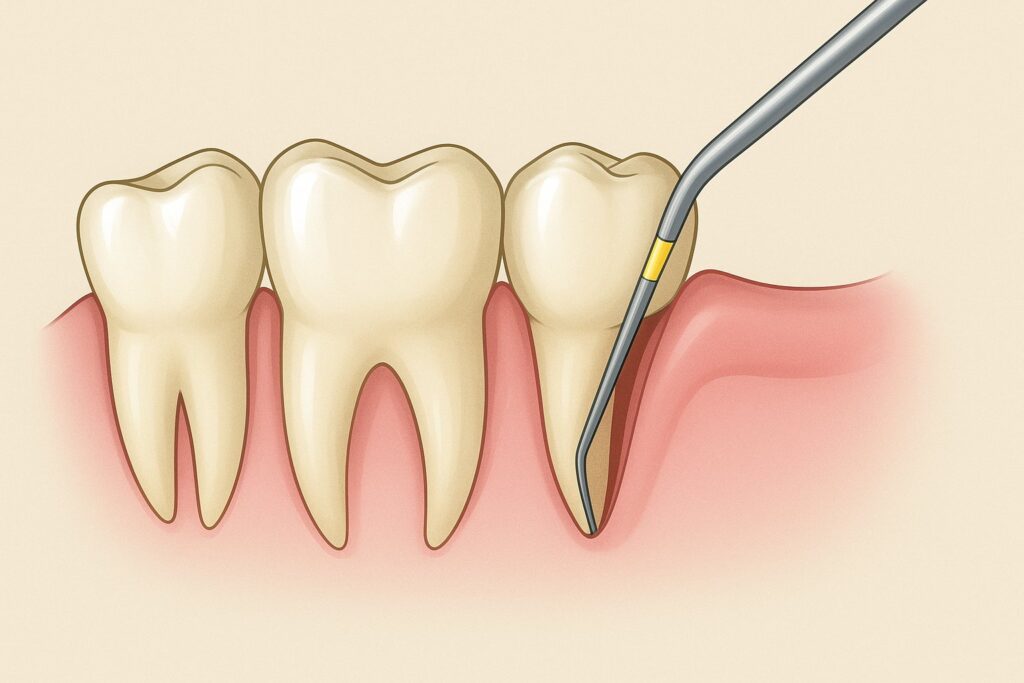

Diagnostyka ropnia opiera się na wywiadzie z pacjentem oraz badaniu klinicznym. Podczas badania widoczne są zaczerwienienie i obrzęk błony śluzowej oraz okrągły lub owalny obrzęk dziąsła. Przy palpacji obszar jest miękki, „falujący” i bardzo bolesny. Zęby mogą być ruchome, a reakcja na opukiwanie dodatnia. Przy sondowaniu kieszonki dziąsłowej lub ucisku dziąsła wydobywa się ropa.

Wyróżnia się cztery miejscowe objawy, na których opiera się diagnostyka topograficzna (określenie ogniska choroby):

- obecność “przyczynowego” zęba;

- nasilenie nacieku zapalnego;

- zaburzenie funkcji ruchowej żuchwy;

- utrudnione połykanie.